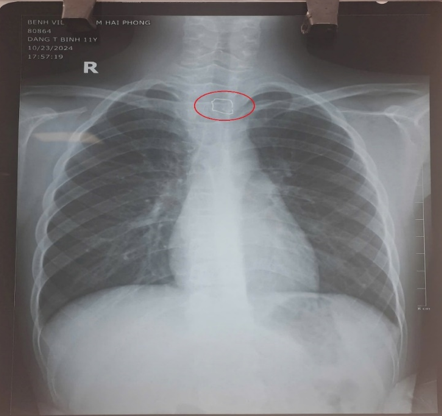

Hình

ảnh XQ dị vật trong đường tiêu hoá

Kết quả trên hình phim, các bác sĩ phát hiện một

vật cản quang là 1 phần dây kim loại hình ảnh giống như mô tả của gia đình nằm

tại vị trí thực quản đoạn cổ.